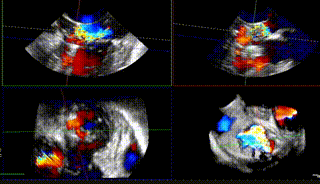

据心外科王圣教授介绍,本次手术在纯超声引导环境下进行,术中患者心脏不停跳,仅需在肋间开一小口,具有低外科损伤与零辐射的特点。该患者为二尖瓣C2区反流,P3脱垂,后叶较短,瓣叶质地欠佳,通过植入一枚ValveClampIIIf型夹子后反流基本消失,导管时间40分钟。术后24H患者脱机转入普通病房,术后48H患者下床活动,目前患者状态良好。

反流基本消失

该患者为原发性二尖瓣反流患者,病变位置偏P3+PC。目前国内外专家对该类非典型病例患者的TEER治疗尚刚刚起步。由于非2区病变患者瓣膜反流位置较偏,操作器械系统输送到达目标位置困难、同时长轴切面与实际夹臂存在夹角,需要使用具有MultiVue(三维重建)功能的超声机器,且手术中缠绕腱索的风险增大,该类患者往往在筛选期就被拒绝难以得有救治,而ValveClamp系统通过心尖操作,选取最佳穿刺点,仅40分钟就植入1枚夹子,术后几乎无反流,充分显示器械操作便利性、高效性。该例手术的成功,标志着河南省二尖瓣反流经导管介入治疗方面取得新突破,该技术未来将造福更多省内二尖瓣反流患者。